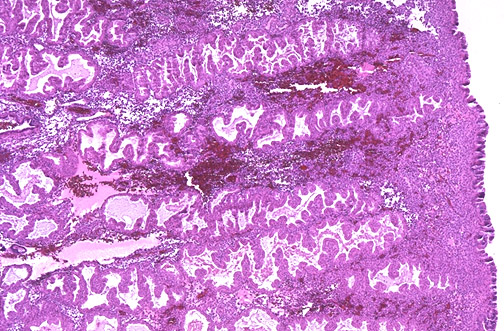

The late secretory endometrium has prominent pink secretions in the glands. Implantation has not occurred, and there is beginning stromal hemorrhage and increasing leukocyte infiltration just prior to menstruation.